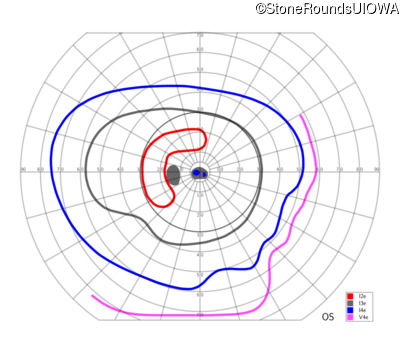

This 52 year old man had normal vision until his mid 30's when he began to have trouble distinguishing colors. the issuing 10 years he had a gradual loss of visual acuity accompanied by increasing photophobia.

| Age at visit: 55 years |

| Age at visit: 58 years |

| Age at visit: 61 years |

| Age at visit: 64 years |